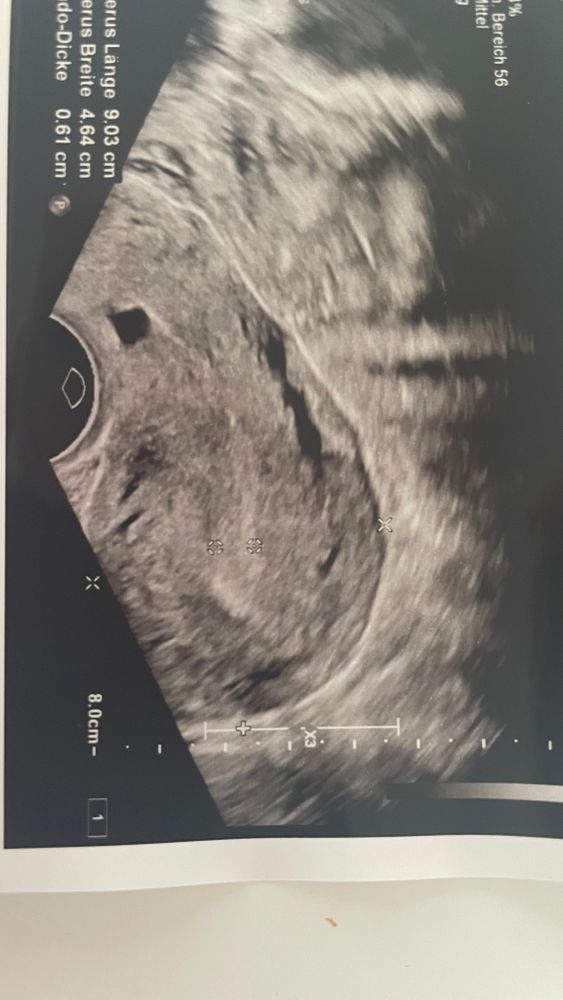

diana rogozina, 6мм это норм Э,ещё подрастет он за три дня до 9-10.у меня хотя на 4 ДЦ был 5,4,но это стандарт,а вот с 6 мм многие беременеют спокойно,так что не переживай.